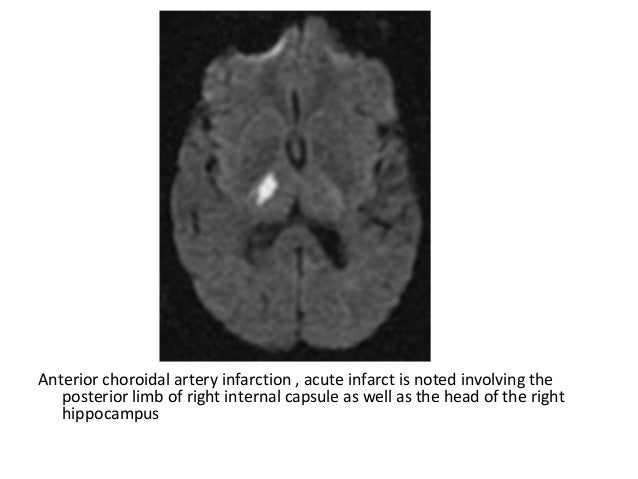

Anterior Choroidal Artery Infarction Bmj Case Reports

casereports.bmj.com